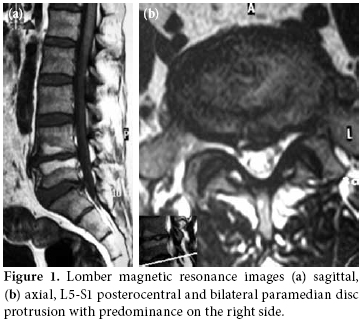

A 49-year-old man complained of pain and swelling of the feet and ankles, particularly on the left side. Two months previously, he had experienced an episode of low back pain radiating down the left leg which developed after an episode of bending and lifting. At that time, he was diagnosed with LDH which was confirmed by magnetic resonance (MR) imaging. The lumbar spine MR images showed L5-S1 disc protrusion in the posterocentral region and in bilateral paramedian regions which was more apparent on the right side (Figure 1). His pain decreased after several days of bed rest and analgesic treatment. One month later low back pain, aching and stiffness developed in the joints of both ankles and feet and was accompanied by dorsal hyperalgesia and allodynia of the left foot. The aching was exacerbated by local pressure or attempted foot movement. Over the next month the symptoms steadily worsened to the point of an inability to bear any weight on the right foot. Mild swelling of the feet, edema, and hyperhydrosis of the left foot were also noted. Ankle motion was restricted near the end of range. There was a complaint of low back discomfort. Straight leg raising on the left side was only 45 degrees. There was a suggestion of mild plantar flexor weakness (4/5, 0 to 5 scale) on the left, but extreme pain on palpation of the left lower extremity prevented reliable motor strength and sensorial evaluation. The remainder of the neuromuscular examination was unremarkable. Rectal tone was intact, and pulses were normal. The patient had no history of trauma. Past medical history, family history and a review of systems were unremarkable revealing no indication of endocrine, rheumatologic or other systemic diseases.

Routine laboratory investigations disclosed no abnormalities. Electromyography disclosed involvement of the left S1 root (gastrocnemius muscle had 2+ waves with mild decreased motor unit numbers) and corresponding paraspinal muscles suggestive of preganglionic damage; sensory and motor conduction was normal. Foot radiographs showed a pattern of osteopenia consistent with left CRPS (Figure 2). Technetium-99m methylene diphosphonate (Tc-99m MDP) three-phase bone scintigraphy (TPBS) confirmed the clinical diagnosis of bilateral CRPS by detecting the mild or intense increased activity uptake in a dynamic, early blood pool, especially in delayed static images (Figure 3).